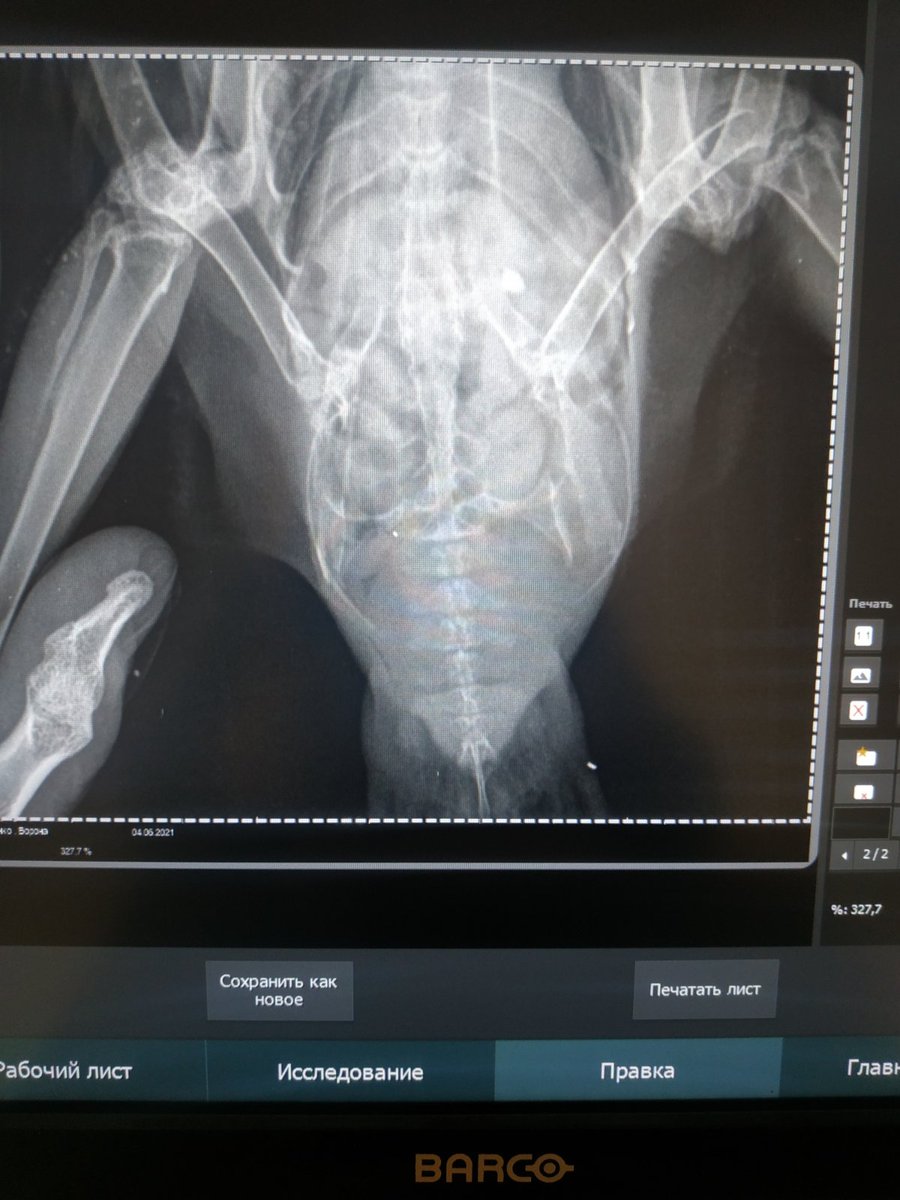

vseprostoe907 Опубликовано 8 июня, 2021 Автор #6 Опубликовано 8 июня, 2021 Добрый день Всем! Вот снимки птички.

Zosia Опубликовано 10 июня, 2021 #7 Опубликовано 10 июня, 2021 Почти наверняка у птицы- пуля. Я сделала поконтрастнее снимок. Пока- ждем. Все что вам уже ранее написали- кальций, витамины группы В- принимаете. Вместо фуросемида- диакарб. Доза 3 мг на каждые 100 гр веса в сутки. Доза разбивается на 3 приема. Курс- 5 дней, потом перерыв 35 дней и допустим второй курс 3 дня. По фото- птиц истощен. Но 450 гр- не соответствует этому фото. Поэтому взвесьте птицу ТОЧНО.